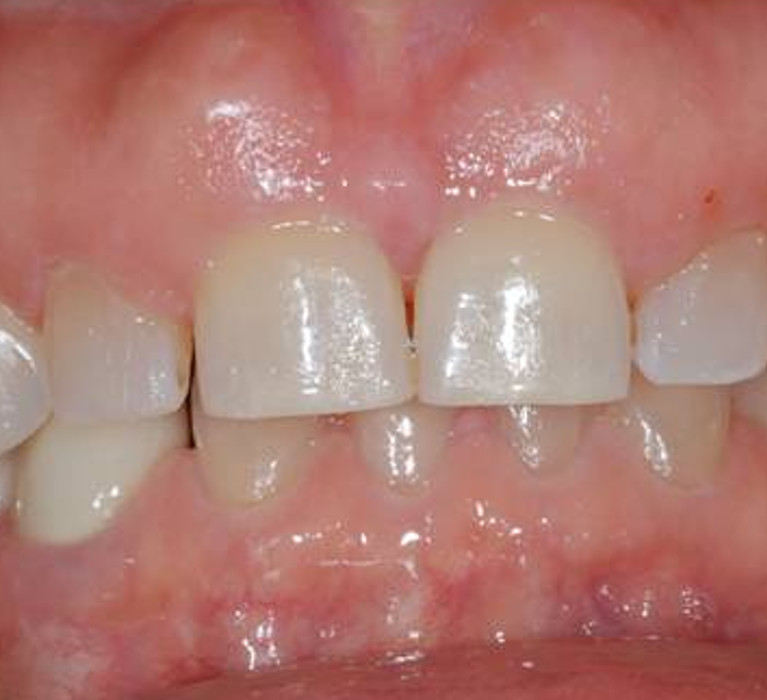

Cosmetic Crown Lengthening

Before